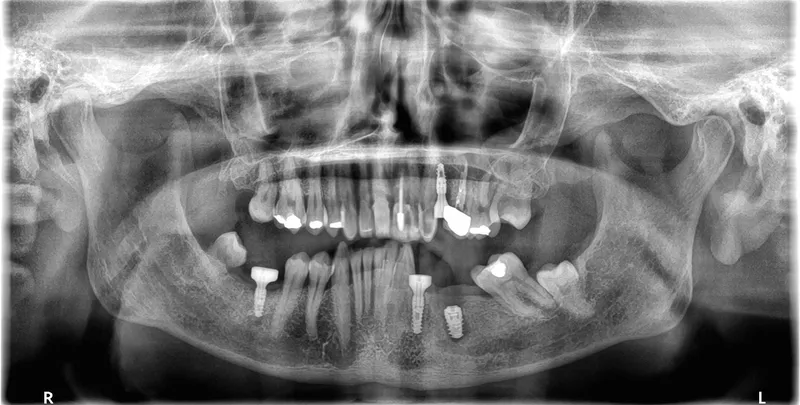

1. Panoramic view showing severe bone loss around tooth 15, confirming hopeless prognosis.

1

9. Panoramic radiograph taken on the day of implant placement.

9